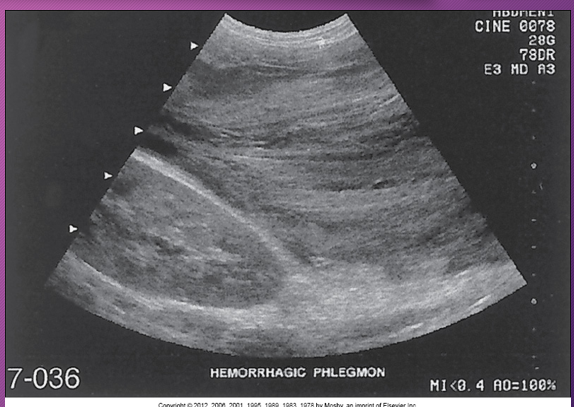

Hemorrhagic pancreatitis is a rapid progression of ______ pancreatitis with _______ of pancreatic ______ and subsequent __________

rapid; acute; rupture; vessels; hemorrhage

In _______ pancreatitis, there is diffuse _____ destruction of the pancreatic substance caused by a sudden escape of ______ pancreatic ________ into the ______ parenchyma

hemorrhagic; enzymatic; active; enzymes; glandular

Pancreatic enzymes cause focal areas of fat ______, _____ and ______ the pancreas, which leads to _____ of pancreatic ______ and _______

necrosis; in and around; rupture; vessels; hemorrhage

Patients with ______ pancreatitis has sudden _______ destruction of the pancreas AFTER an ______ binge or an excessively _____ meal

hemorrhagic; necrotizing; alcoholic; large

Sonographically, hemorrhagic pancreatitis depends on the ____ of the hemorrhage

age

Sonographically, a ______ necrosis may be seen as a ___- defined, ________ mass in the area of the pancreas

fresh; well; homogenous

Sonographically, at ____ week, the mass (hemorrhage) may appear ____ with ____ elements or _______

1; cystic; solid; septation

Sonographically, after _____ weeks, the hemorrhage may appear ______